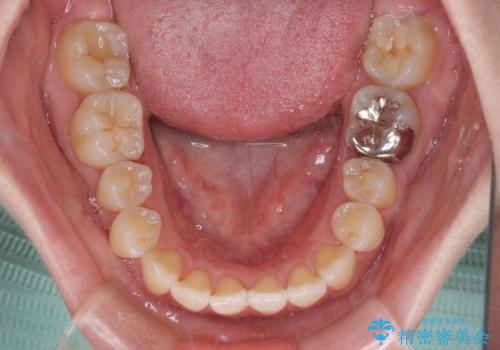

口元の突出感を改善 インビザラインによる非抜歯矯正

- 前歯がデコボコした上に口元が閉じにくいことを気にして来院された患者様です。

IPR(歯と歯の間を削る)と側方拡大では口の閉じにくさは改善できそうになく、一方で抜歯矯正を行うほどの突出感は認められませんでした。

親知らずを全て抜去し、歯列全体を後方に移動させることで口元の閉じにくさいを改善していくこととしました。

インビザラインでの歯列全体の後方移動は時間がかかりますが、しっかりと装着時間を守っていただいたので、スッキリとした口元に仕上げることができました。